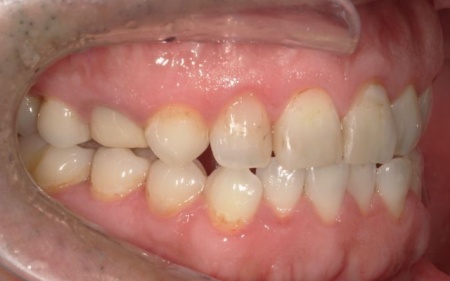

40代男性 長年放置していた虫歯や根尖性歯周炎などの口腔トラブルを全体的に治療した症例

「虫歯を長年放置してしまったので治療をしたい。また、見た目や噛み合わせの改善などを含めた、全体的な治療も行いたい」とご相談いただきました。

患者様は、10年ぶりに歯科医院を受診したとのことです。

レントゲン撮影をして詳しく検査したところ、複数の小さな虫歯が見られました。

また右上奥歯には、歯根の先に炎症が起きて膿が溜まる根尖性(こんせんせい)歯周炎が認められます。

さらに、左上奥歯(第1大臼歯)は温存が難しい状態でした。